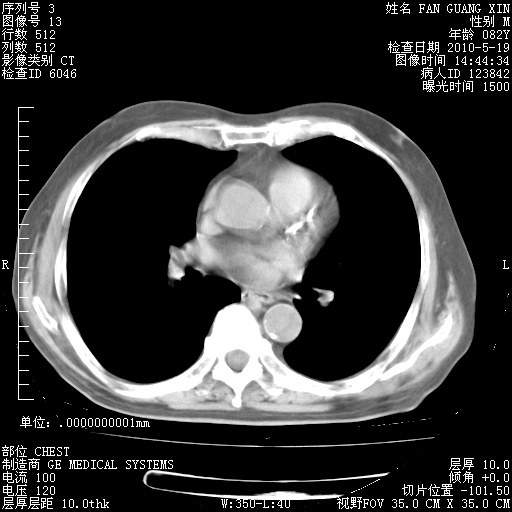

治疗3周后的肺部CT纵隔窗